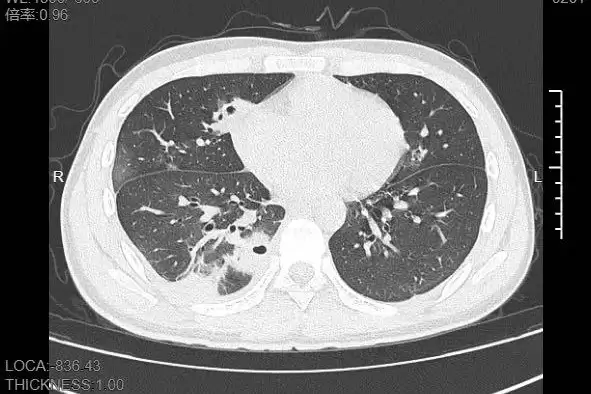

接诊的呼吸与危重症医学科丁群力主任医师发现其症状异常,立即安排CT检查。结果显示:小林肺部出现十余个空洞,部分肺组织已坏死,这是典型的血源性肺脓肿。